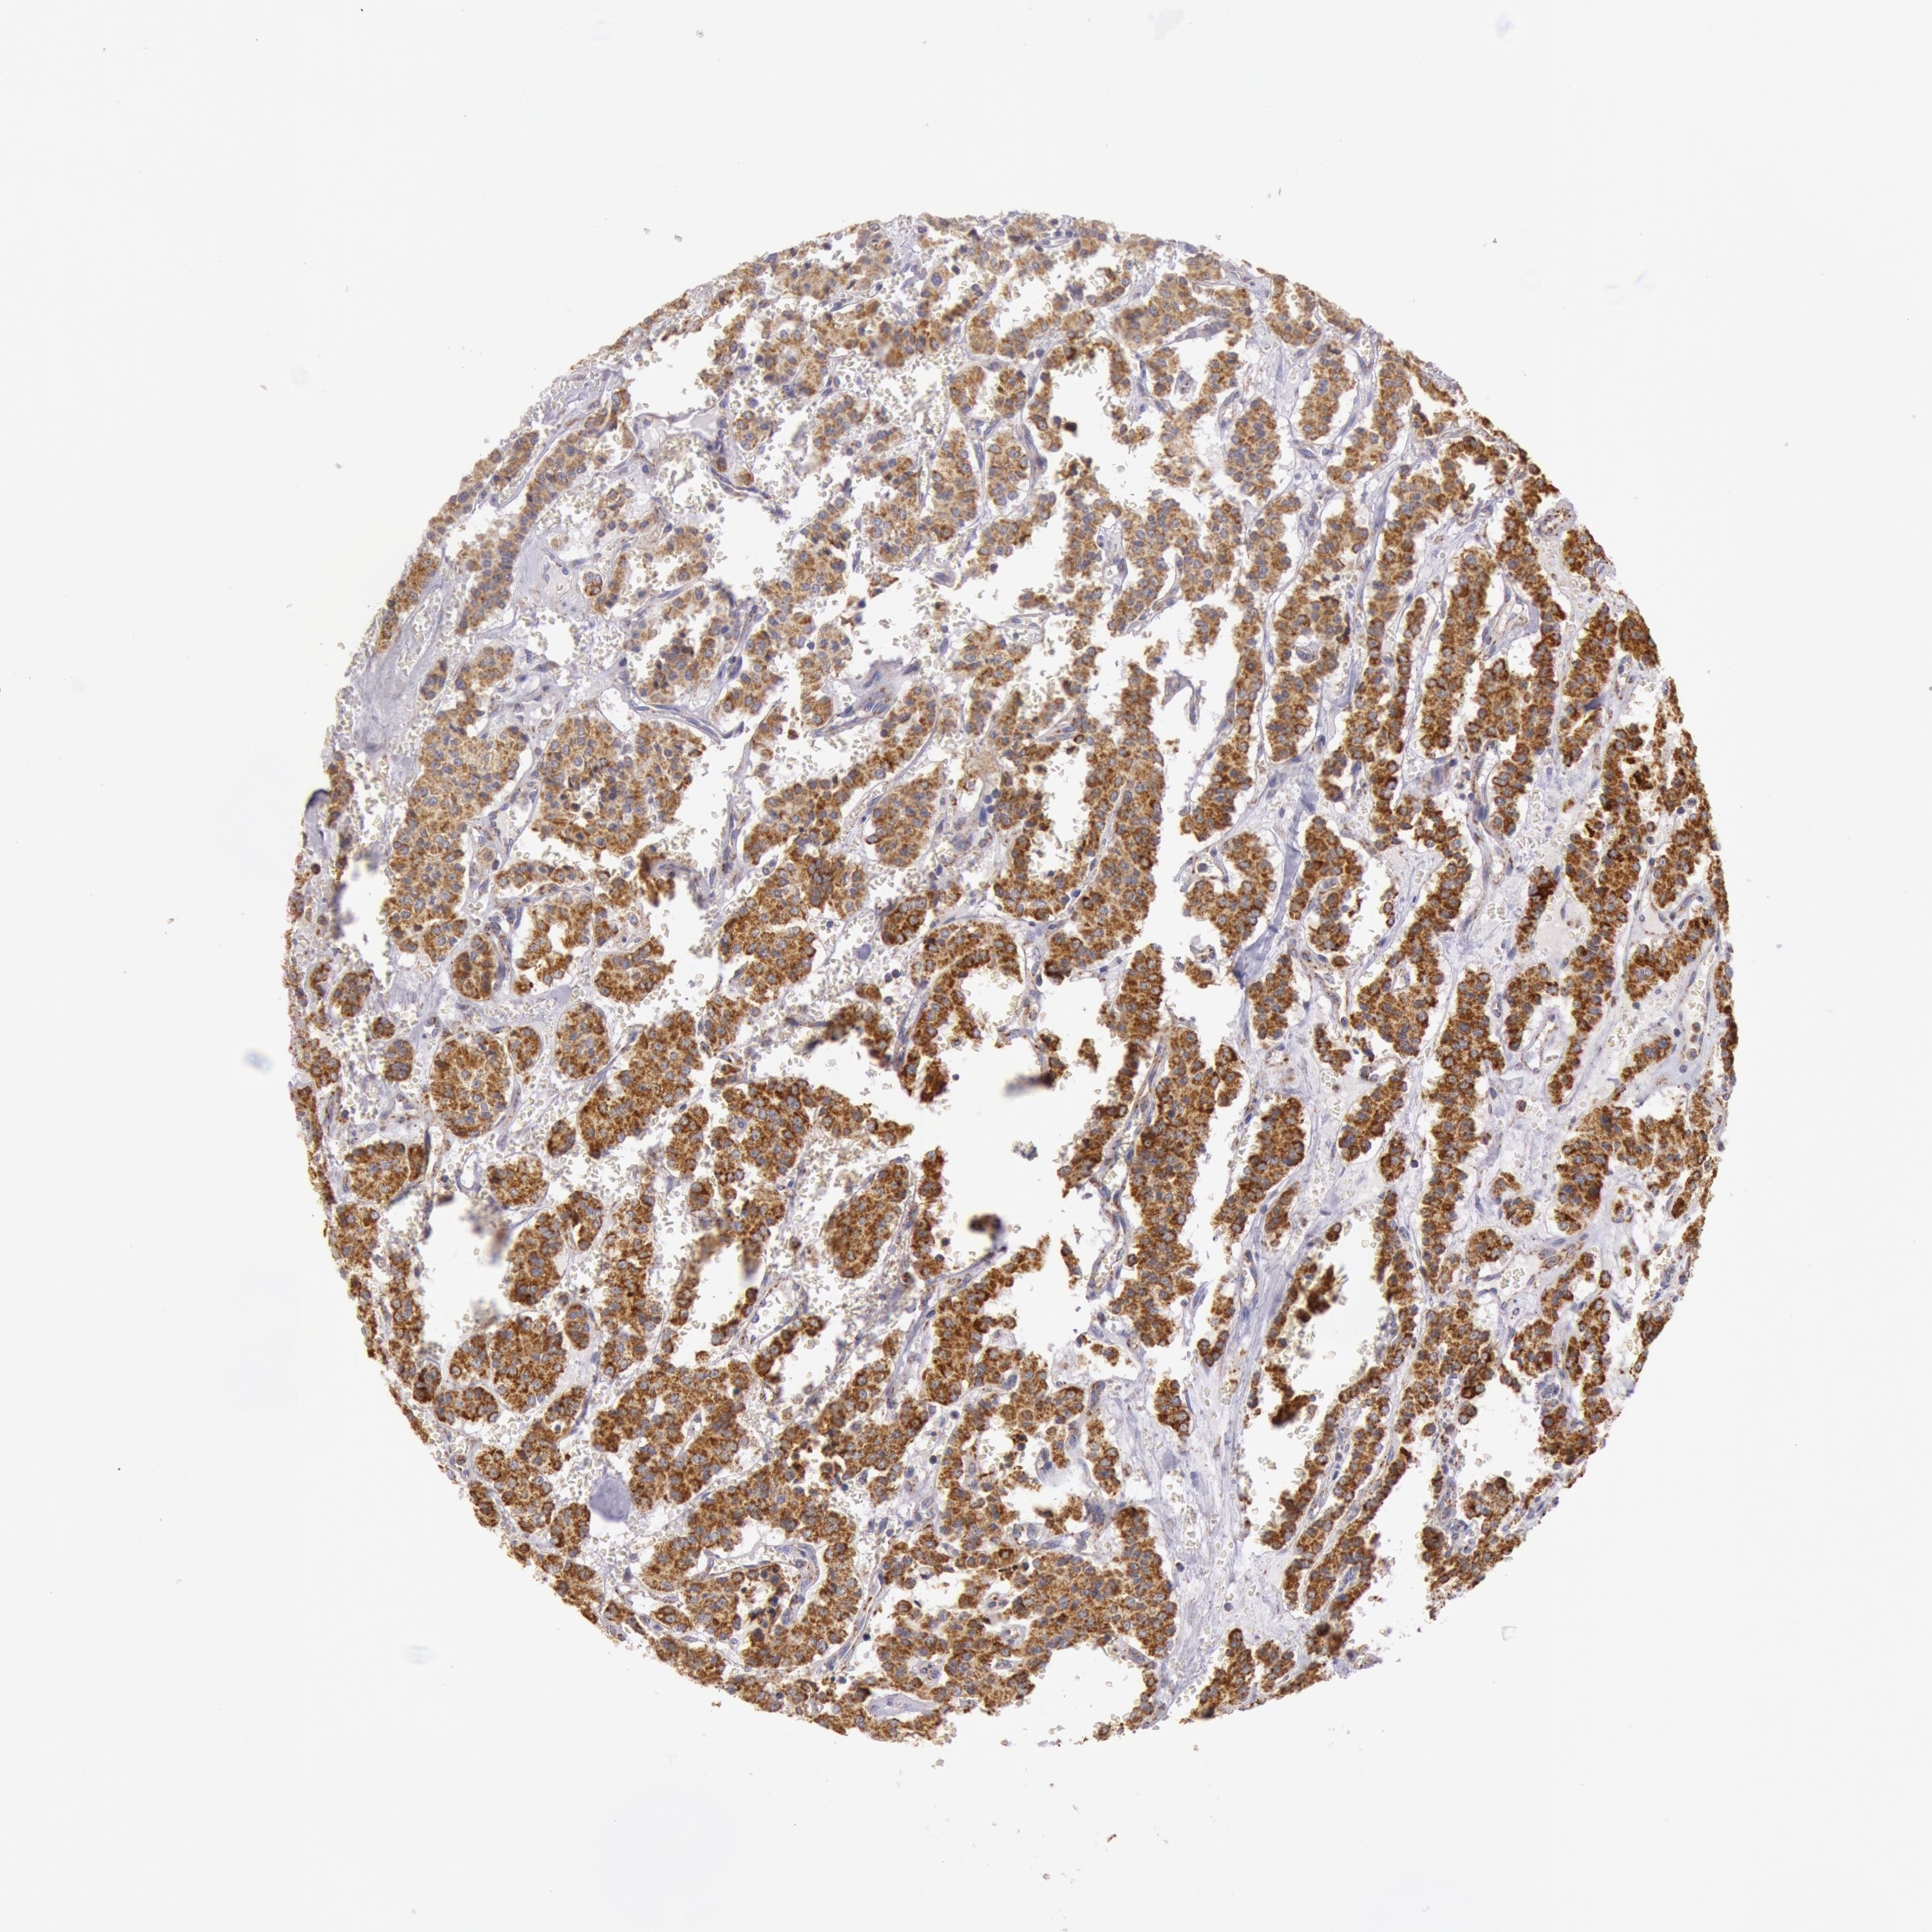

CARCINOID - Protein expressioni

A mouse-over function shows sample information and annotation data. Click on an image to view it in a full screen mode. Samples can be filtered based on level of antibody staining by selecting one or several of the following categories: high, medium, low and not detected. The assay and annotation is described here.

Antibody stainingi

Antibody staining in the annotated cell types in the current human tissue is reported as not detected, low, medium, or high, based on conventional immunohistochemistry profiling in selected tissues. This score is based on the combination of the staining intensity and fraction of stained cells.

Each image is clickable and will lead to virtual microscopy that enables deeper exploration of all samples and also displays staining intensity scores, fraction scores and subcellular localization as well as patient and tissue information for each sample.

Antibody HPA001247

Staining

High

Intensity

Strong

Quantity

>75%

Location

Cytoplasmic/membranous

Carcinoid, malignant, NOS